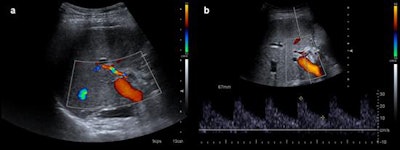

Color Doppler ultrasound exams are routinely performed at 24 to 48 hours on the seventh day, the first and third month after transplantation, while CT and MR images are acquired based on the Doppler ultrasound findings even in the absence of abnormal liver function, they explained in an in-depth article posted on 14 August by Insights into Imaging.

Because vascular complications appear early after surgery, Doppler ultrasound should be performed by experienced staff; diagnostic angiography is seldom performed.

"Stenosis may progress to thrombosis. So, stenosis and thrombosis are two entities of the same spectrum of vascular complications of liver transplantation," the authors wrote. "Stenosis can lead to splenic steal artery syndrome. It usually occurs in the first three months, but this time shows differences between patients, describing cases that happen even several years after surgery. Doppler ultrasound is the most useful technique to show this complication, as explained for thrombosis."

In the first three days after liver transplantation, an increased resistance index of the hepatic artery (greater than 0.8) is found in approximately 50% of the patients, they pointed out. If found, it should be monitored until it has normalized, typically on the fourth day after transplantation. Although the severity of the described findings correlates with the degree of the stenosis, ultrasound does not allow proper quantification of this, and the technique of choice is CT angiography. In addition, CT allows proper evaluation of patients with a poor sonographic window while MR angiography is a limited technique because of a relatively high false-positive rate, they added.